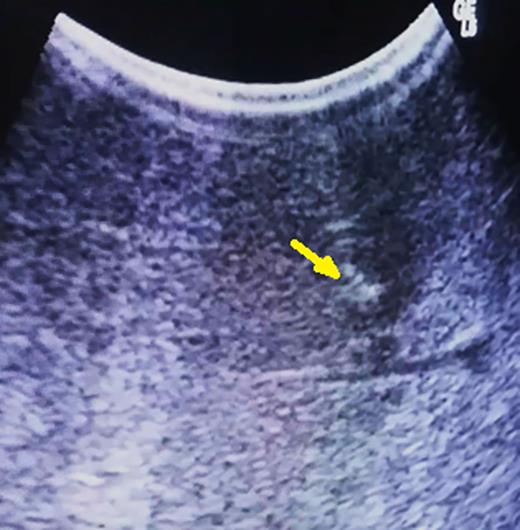

Under ultrasonography guidance, a 30-gauge needle is inserted until reaching the tumor (Fig. 2a). At this time, 5 ml of methylene blue is inserted, and the needle is retracted from the liver. The first result is that a small area around the tumor and the lesion itself will immediately change its echographic characteristics, becoming much more hyper-reflective and easily identifiable by ultrasonography (Fig. 2b).

(A) Methylene blue injection under ultrasonographic guidance and (B) easily identifiable methylene blue-injected lesion with hyper-echoic pattern (arrow).